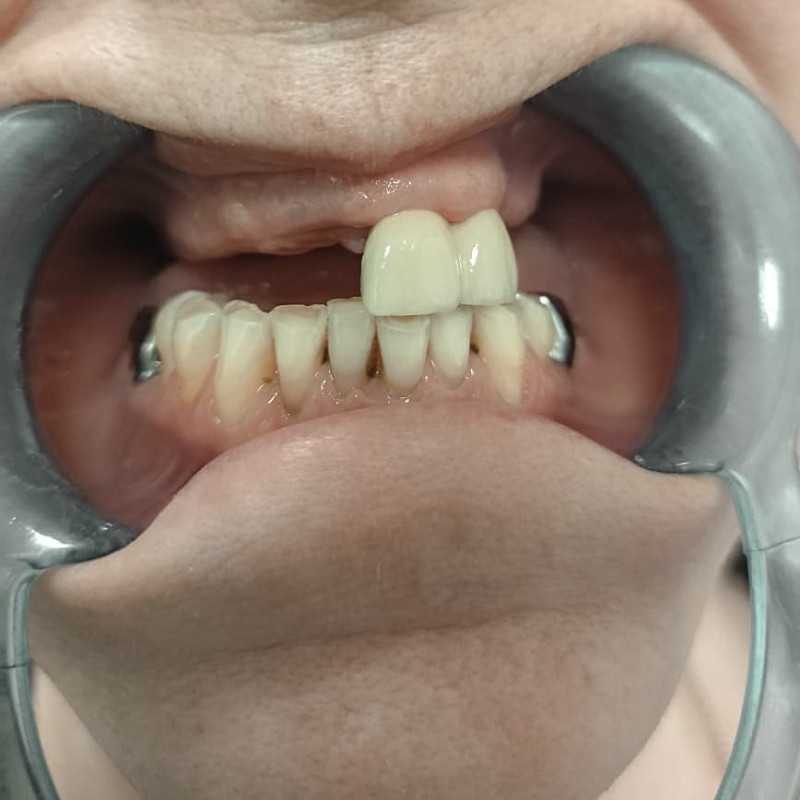

Жалобы: на отсутствие зубов, неудовлетворительную эстетику зубных рядов, невозможность жевать, снижение высоты прикуса. Что сделано: удаление зубов на в/ч и н/ч, установка имплантатов Bredent Sky и одномоментное протезирование акриловыми протезами с опорой на имплантаты по протоколу Fast & Fixed (зубы за один день). Через 8 месяцев проведена работа по замене протезов на постоянные металлокерамические. Что получил пациент: красивые и ровные зубные ряды, возможность нормально питаться с первого дня после операции, поднята высота прикуса, теперь не стесняется улыбаться.